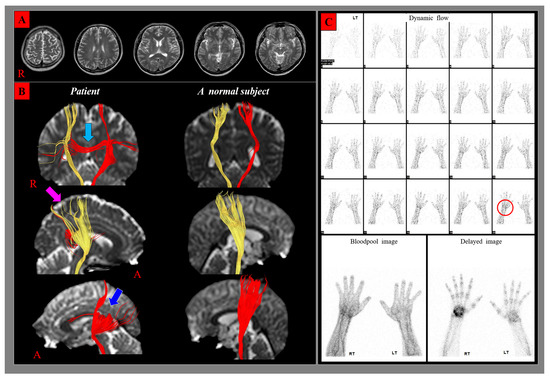

| Diffusion Tensor Tractography | ||||

|---|---|---|---|---|

| CST | Patient | Control Subjects | p-Value | |

| FA | RT | 0.47 | 0.49 ± 0.02 | 0.21 |

| LT | 0.46 | 0.47 ± 0.02 | 0.39 | |

| ADC | RT | 0.86 | 0.85 ± 0.03 | 0.26 |

| LT | 0.84 | 0.84 ± 0.02 | 0.29 | |

| FN | RT | 1654 | 1711.15 ± 215.18 | 0.43 |

| LT | 1203 | 1690.44 ± 194.62 | 0.01 * | |